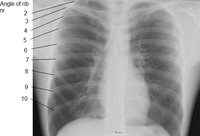

![]() القفص الصدري البشري. الأضلاع تتصل بالعمود الفقري، ومنه تنحني للأسفل وللأمام لتشكل قفصًا واقيًا حول القلب والرئتين. ويوجد في جسم الإنسان 24 ضلعًا، 12 ضلعًا في كل جانب. (المصدر: Gray's Anatomy of the Human Body, 20th ed. 1918) | |

الضلع Rib واحد من العظام الأربعة والعشرين التي تحيط بالصدر في جسم الإنسان. وهناك اثنا عشر ضلعًا في كل جانب من جانبي الجسم، يَتصِل كل واحد منها بالعمود الفقري بوساطة وصلات تسمى الفقرات. وفي مقدمة الجسم، ترتبط الأضلاع السبعة العلوية في كل جانب مباشرة بالعظمة الصدرية بوساطة مادة صلبة مطاطية تسمى الغضاريف، وتُسمى هذه الأضلاع، الأضلاع الحقيقية. أما الأضلاع الخمسة التي تحتها وتُسمى الأضلاع الإضافية، فليست مُتصلة بعظمة الصدر بشكل مباشر، بل إن كل واحد من الأضلاع الثلاثة العلوية الإضافية، مُتصل بالضلع الذي يعلو الغضروف. أما الضلعان اللذان يقعان في الأسفل، فإنهما مُتَصلان بعظمة الظهر. ويُعرفان باسم الضلعين السائبين. وتحتوي الفراغات الموجودة بين الأضلاع، والتي تُسمَّى فراغات بين الأضلاع، على الشرايين والأوردة والعضلات والأعصاب.

تقسيم الاضلاع في الإنسان

- أول سبعة أزواج من الاضلاع تسمى "الأضلاع الحقيقية". وهي متصلة بسشكل مباشر بعظم القص.

- ازواج الاضلاع الثلاثة التالية تسمى بالأضلاع الكاذبة " وهي تتصل بعظم القص بواسطة غضروف.

- اخر زوجين من الاضلاع تسمى " الأضلاع السابحة " وهي متصلة بالعمود الفقري ولا تتصل بعظم القص.

Human ribs (shown in red). It consists of 24 ribs. Left and right of first rib to twelfth rib.